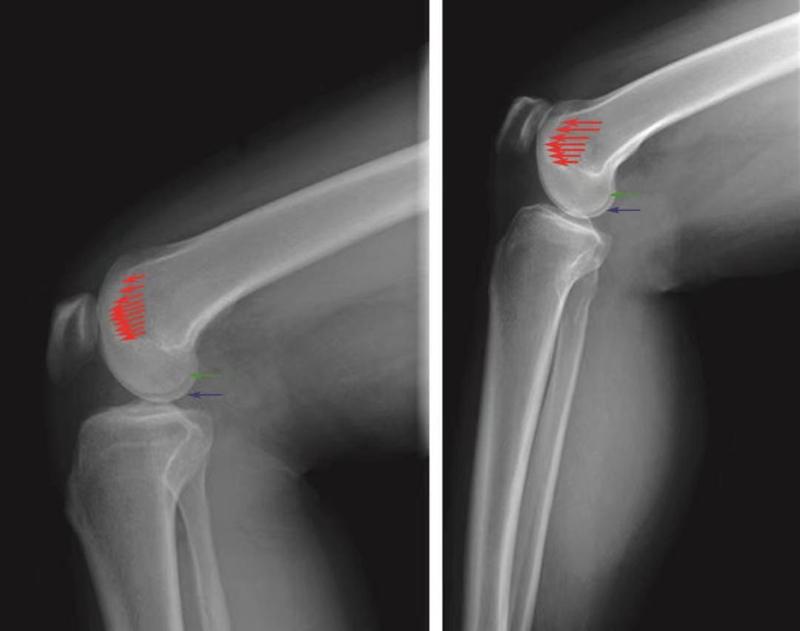

1️⃣ 股骨滑车正常表现:

在标准的X线侧位片上,正常的膝关节滑车形态有以下3个特点(图10):①Blumenssat线延续为股骨滑车沟基底线,该基底线始终位于股骨髁轮廓线的后方,意味着股骨滑车沟低于股骨滑车的侧壁;②滑车沟基底线的最高点不超过股骨干前方皮质的延长线;③股骨内外滑车轮廓线几乎重叠,只显影为一条轮廓线。

图10 正常股骨滑车侧位X线片的特点

滑车沟基底线(红色箭头)位于股骨外髁轮廓线(绿色箭头)和内髁轮廓线(蓝色箭头)的后方和下方;滑车沟基底线的最高点不超过股骨干前方皮质延长线;股骨内外髁轮廓线重叠